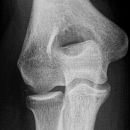

Ellenbogen seitlich nach N. Stjepanovic

Patient wird wie Ellenbogen lateral gelagert; jedoch Oberarm mit einem 10°Keil anheben und gleichzeitig auch den Unterarm um 15° mit einem Keilkissen anheben. Kassette auf den Kissen und unter dem Ellenbogen legen, so dass sie auf nur auf der einen Ecke aufliegt.

Senkrecht zum Tisch keine Winkel einstellen.

Aufgrund der Winkelung von 10° bzw 15° erscheinen paar Strukturen verkürzt.

Durch diese exakte Einstellung von N. Stjepanovic ist das humero-ulnar-Gelenk sehr gut einsehbar.